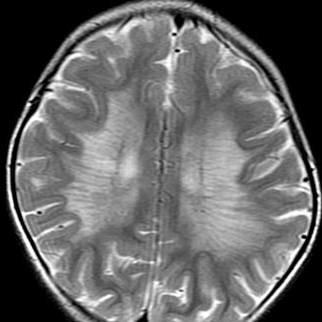

• Symmetric, confluent, deep WM (spares U-fibers) Symmetric, confluent, deep WM (spares U-fibers)

• “ “TigroidTigroid” or “ ” or “leopardleopard” pattern of WM sparing along PV spaces ” pattern of WM sparing along PV spaces

• No enhancement No enhancement